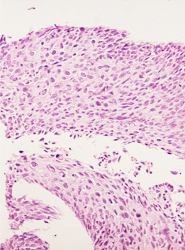

El resultado de una valoración colposcópica de paciente con lesión displásica siempre será confirmado por el estudio histopatológico que realiza el médico anatomopatólogo (estudio de la biopsia tomada en la colposcopía) . A continuación presentamos imágenes histológicas con sus diagnósticos.

• Franca anisocitosis y anisocariosis, hipercromasia y varias figuras mitoticas atipicas en el contexto de las celulas neoplasicas.